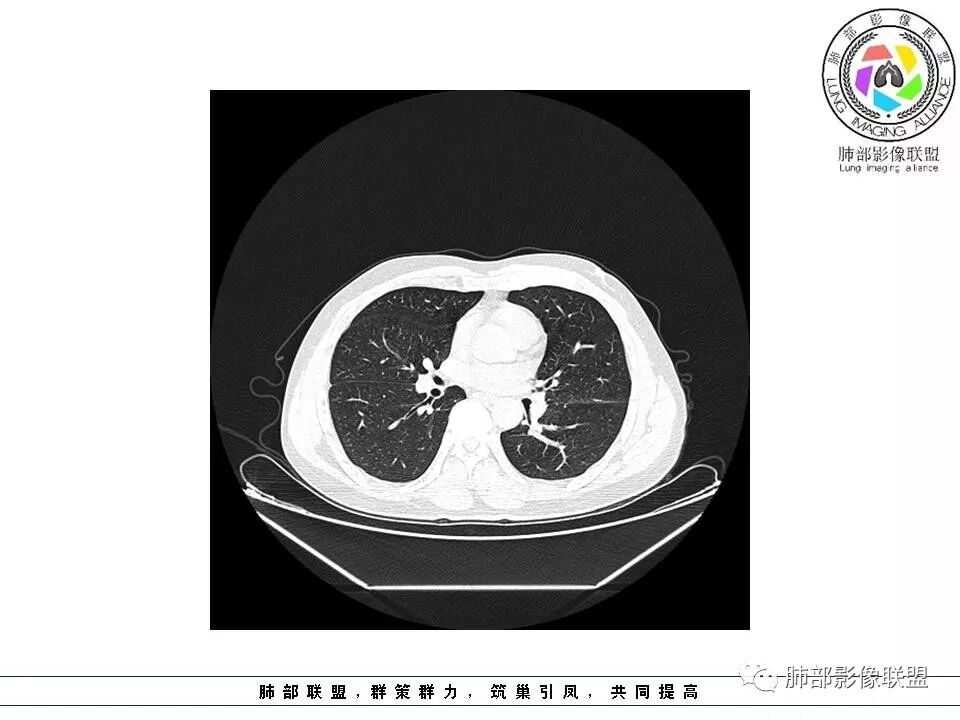

这个病例,它是边缘有一些恶性的特点出来了,但是可能重点关注的部位不同。专注于那些实性成分去了,没看到边缘征像。他确实有一些良性的征像在那里,恶性迹象不明显,或者某些层面出现恶性征像。

原位癌和跟腺瘤样增生,一般属于肿瘤的休眠期状态,比较早期的,就是它的生长速度,非常非常缓慢。

甚至有一些它可以一直静止不动,还有一些他,甚至可能还有凋亡,它自己慢慢萎缩的。

目前这种的,一年两年观察就是复查一次,观察发现没变化,几乎以后都不动了,不再观察了。